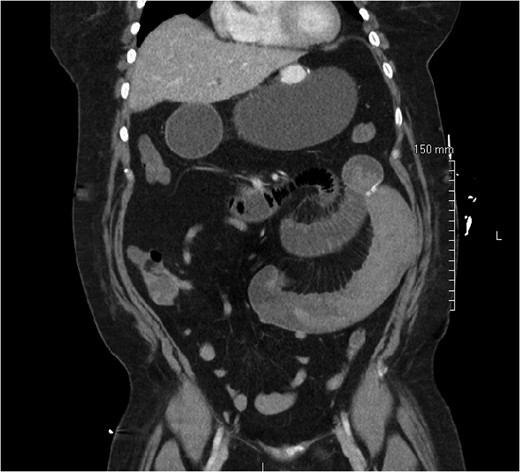

On post-operative day 1, she complained of nausea, vomiting and abdominal pain, though symptoms were consistent with an expected post-operative course. On post-operative day 2, however, she developed a leukocytosis of 15 600/mm3 and an intermittent tachycardia ranging from 85 to 118 bpm. An abdominal CT was obtained, which demonstrated a SBO with a transition point distal to the jejunojejunostomy anastomosis (Fig. 1). The patient was taken to the operating room for diagnostic laparoscopy. Upon initial inspection, there was no evidence of a mechanical cause for obstruction such as kinking or adhesions. However, the bowel proximal to the common channel appeared dilated and discolored (Fig. 2). Esophagogastroduodenoscopy (EGD) was performed to inspect the luminal mucosa, which was pink and well-perfused. Inspection distal to the jejunojejunostomy revealed a 50 cm section of bowel that was firm and appeared to be the point of obstruction. An enterotomy was made in the proximal common channel, which revealed a large intraluminal clot (Fig. 3). This was removed piecewise with a combination of suction and manual extraction (Fig. 4). There was no evidence of active bleeding or leakage from the jejunojejunostomy anastomosis. Due to the friability of the intestinal walls and absence of active bleeding, the anastomosis was not revised and the enterotomy was primarily closed.

Dilated, friable small bowel of the common channel proximal to the site of obstruction with discoloration due to intraluminal clot.